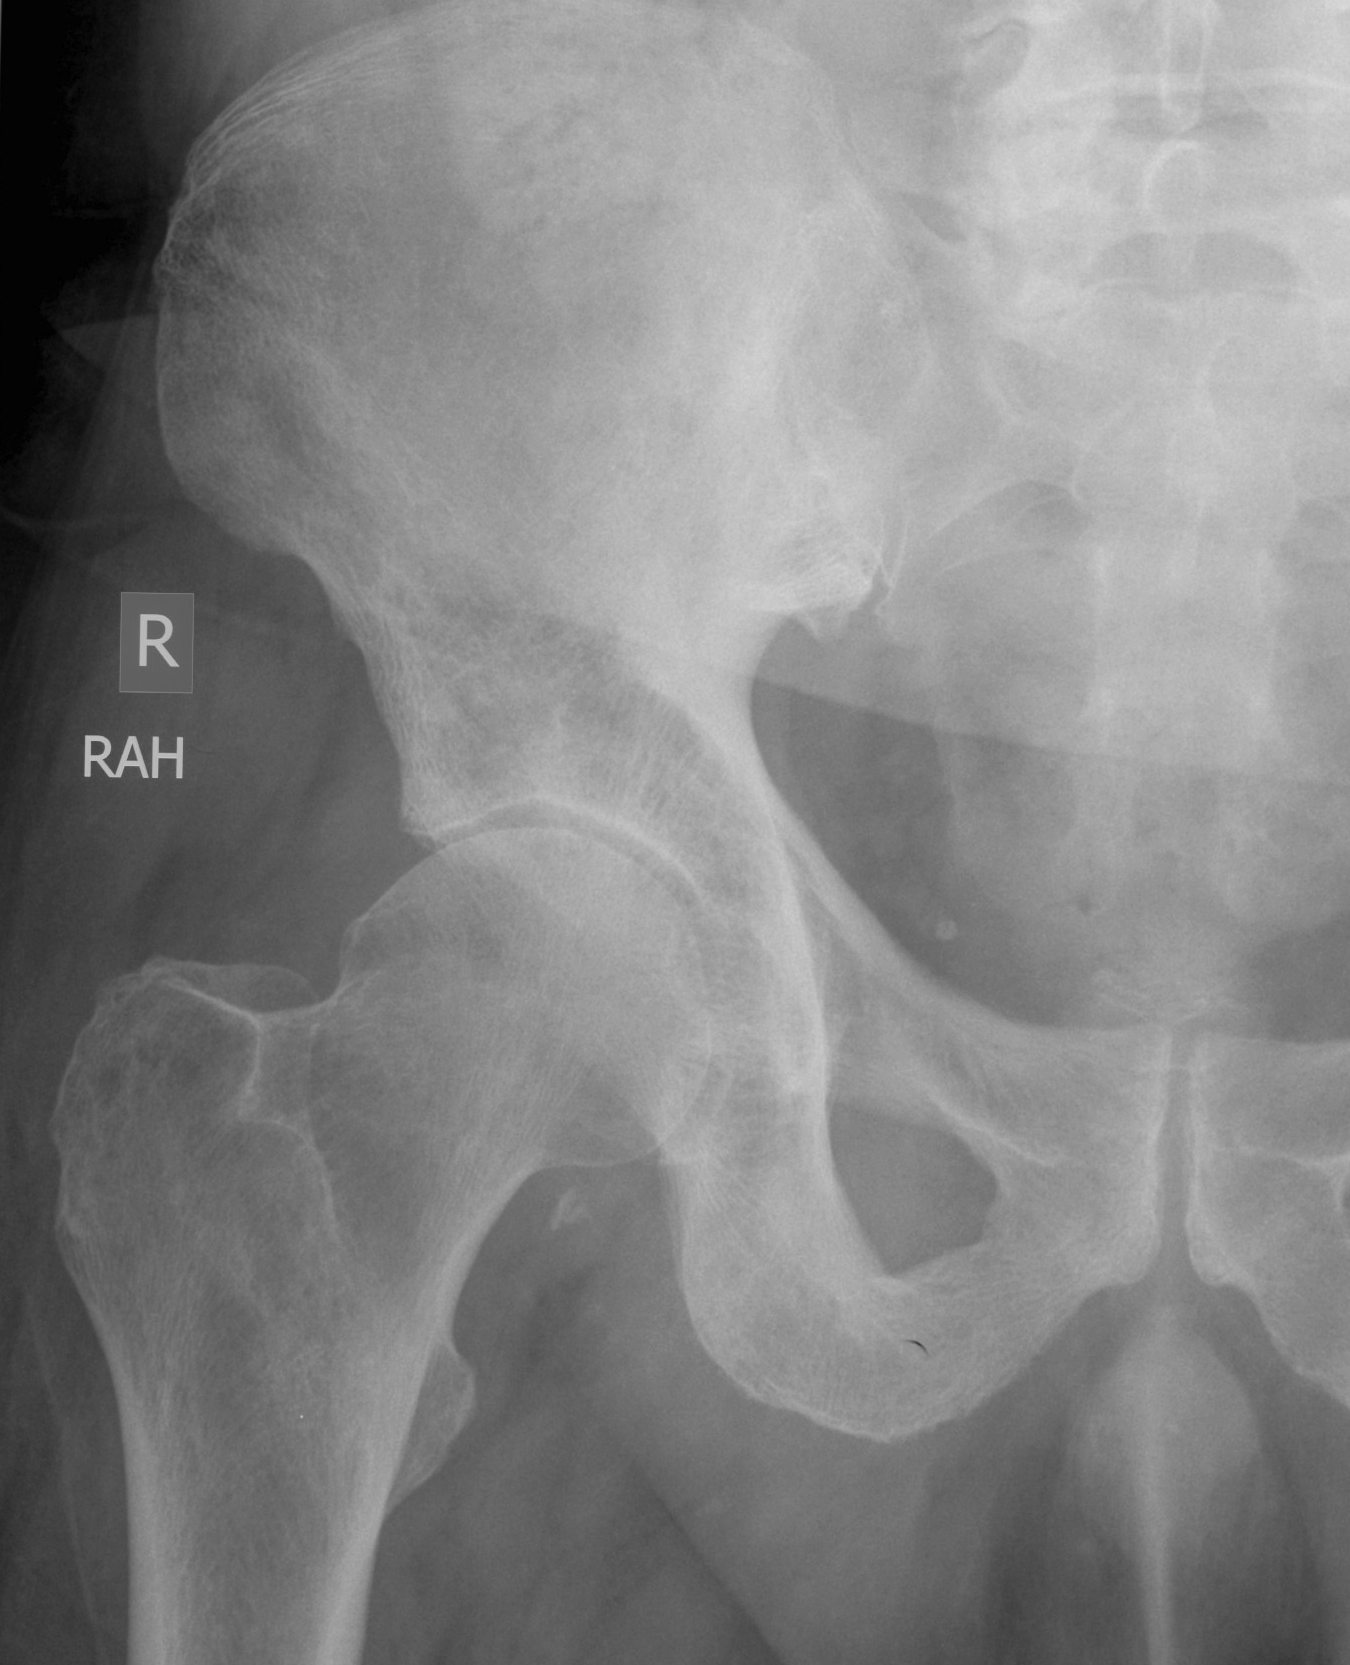

Paget disease pelvis Image Paget's Disease Hip Symptoms headaches and hearing loss when paget’s disease affects the skull. hip pain, which may occur when paget’s disease affects the pelvis or thighbone. what are the symptoms and signs of paget’s disease of the bone (osteitis deformans)? many people with paget's disease do not have any symptoms at all. for paget's disease of bone, some. Paget's Disease Hip Symptoms.

From radiopaedia.org